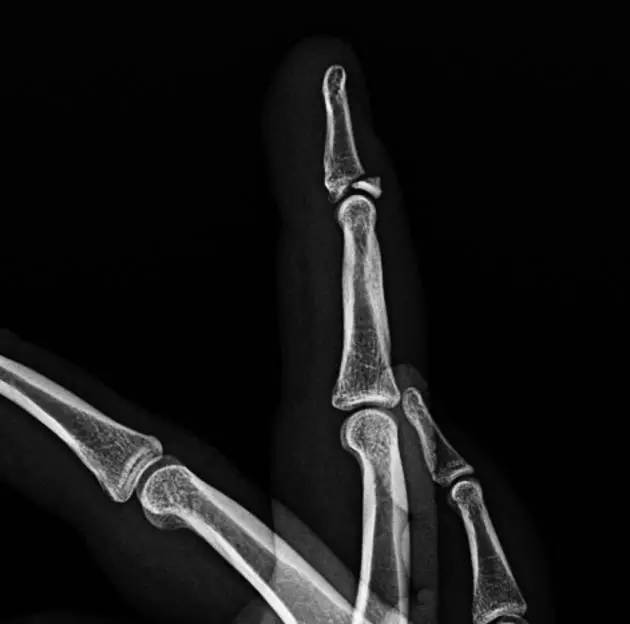

8. Mallet Finger/Baseball finger

即锤状指。远节指间关节的屈曲畸形,是由附着远节指骨伸肌腱分离引起,也可由伸肌腱的直接损伤继发引起。或由远节指骨撕裂性骨折引起肌腱嵌入骨折端引起。

(来源:orthoinfo- AAOS)

(来源:Radiopaedia)